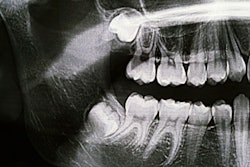

The device uses targeted heat to stop third molars from forming in children, potentially eliminating the need for future extractions.